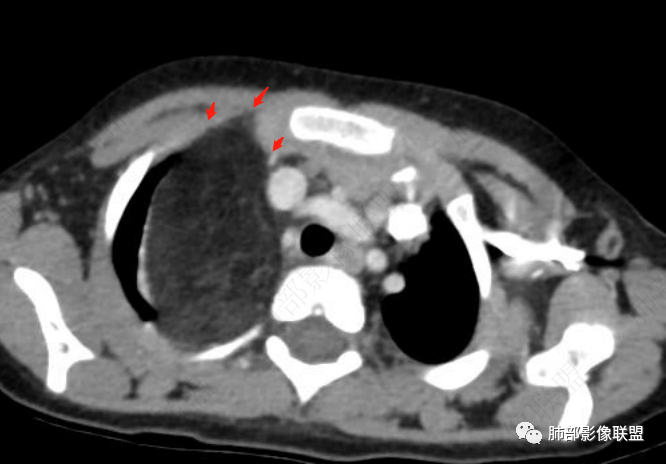

病灶属于交界区,主体位于肺内,占位效应明显,前方突入胸壁,胸腺受压变形,胸膜显示欠清楚;病灶包绕上叶肺动脉;似乎有体动脉供血。符合肺内的点:包绕上叶肺动脉分支;符合纵隔的点:前方似乎突入胸壁,与胸腺关系比较密切,但是与上腔静脉的关系提示病灶不支持纵隔来源,前纵隔的常规会将上腔静脉受压后移、外移,这是不符合的。

从这个角度符合肺内的,有一点不太踏实的是:似乎突入前胸壁。

2.肺动脉穿行也许是肺内来源最重要支持点!